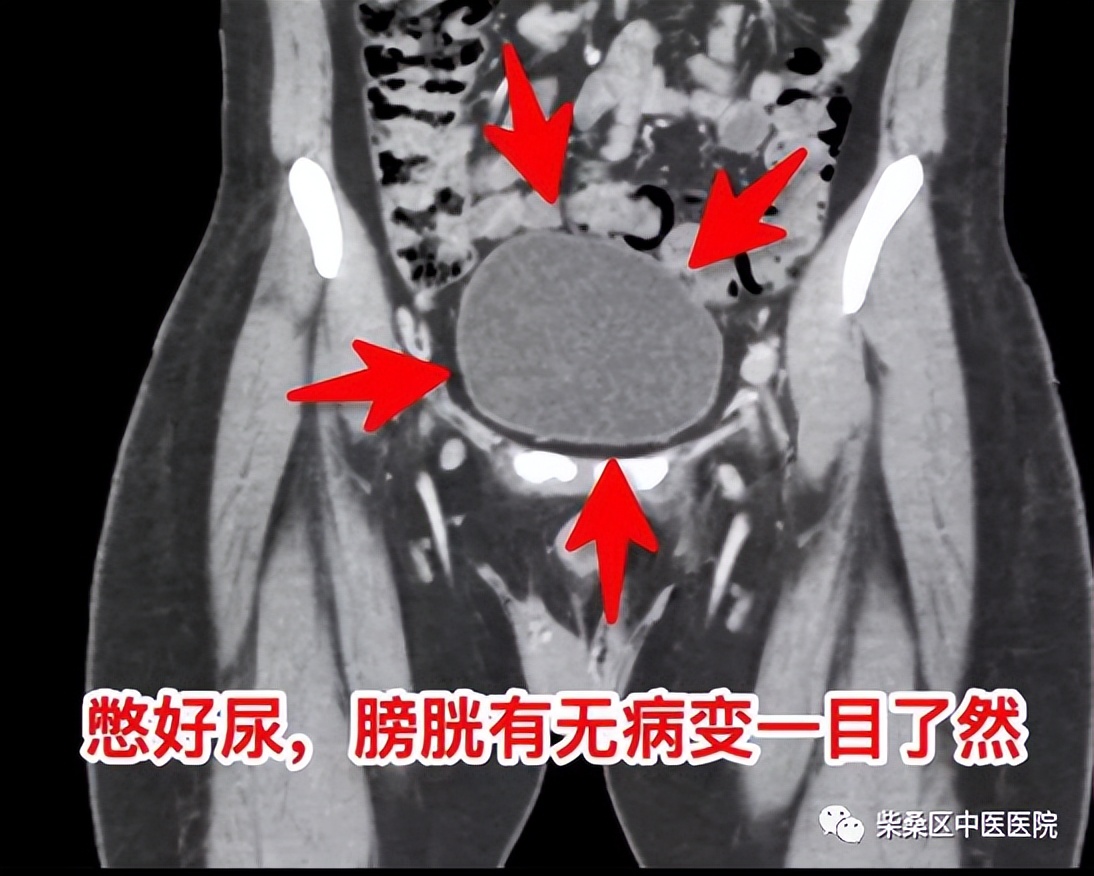

适当的憋尿,有利于将膀胱充盈起来,从而更好地观察到膀胱大小、形态、膀胱壁厚度,有没有病变及病变形态、大小、密度等情况。

正常膀胱充盈可见水样密度影,还可以看见膀胱壁薄厚,正常充盈时,膀胱壁约5mm。例如膀胱有肿瘤、结石以及膀胱憩室等疾病时都需要在膀胱充盈状态时才会显示。另外在女性盆腔CT的检查中,充盈饱满的膀胱可以与子宫附件囊肿进行有效区分。

所以在进行盆腔CT检查之前可以适当的喝一些温开水,加快人体的新陈代谢,有助于尿液的分泌。使膀胱充盈饱满从而可以提升影像科医生对泌尿系统检查结果的准确性,更有助于病情的治疗。